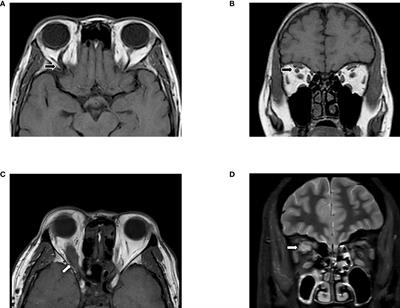

Graves’ orbitopathy (GO) is a disfiguring, inflammatory disease, with an incidence of 10/10,000

Persons, typically associated with autoimmune thyroid diseases, i.e., Graves’ disease and hypothyroid autoimmune thyroiditis. Only in a minority of patients (1-2%) GO is observed in the absence of overt thyroid dysfunction, but still with subclinical signs of thyroid autoimmunity, namely the presence of thyroid-directed autoantibodies. It is well accepted that GO is an autoimmune disease, being the thyroid-stimulating hormone receptor (TSH-R) the major autoantigen. Recently, a major role of the insulin-like growth factor-1 receptor (IGF-1R) has emerged. Depending on the severity and the activity of the disease, GO patients should receive different treatments and their management could be complex. The first line treatment available for patients with moderate-to-severe, active GO is intravenous glucocorticoids plus mycophenolate. However, the recently published guidelines of the European Group on Graves’ orbitopathy (EUGOGO) point out that the optimal treatment is yet to be identified, as none of the available procedures result in a complete long-term response in all patients. In this regard, the research on GO pathogenesis is still ongoing, aimed at comprehending its mechanisms and risk factors and identifying novel therapeutic targets.